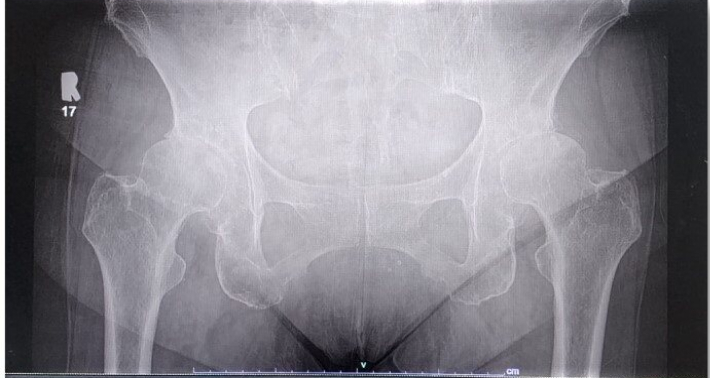

Bilateral hip X-ray

- X-ray showed bilateral hip osteoarthritis